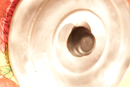

Priscila Felipe | FOTOGRAFIA